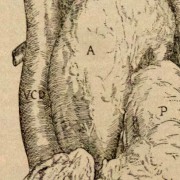

Lilly Ebstein Lowenstein (1897-1966) led a life between science and art, drawing and taking photographs in the fields of Medicine and Zoology. In her work, Lilly combined her technical knowledge of photography and drawing, the study of the sciences and a remarkable talent for aesthetics. She was born in Germany and studied at the Lette-Verein School in Berlin from 1911 to 1914. In 1925, she immigrated with her husband and two children to São Paulo. In 1926, she became an illustrator and photomicrographer at the Illustration and Photography Department at the School of Medicine (USP, as of 1934), which she headed for thirty years after 1932. Lilly collaborated at Instituto Biológico de Defesa Agrícola e Animal (the Biological Institute for the Defense of Agriculture and Animals), from 1930 to 1935, namely in the Avian Pathology Department. A life with art dedicated to the research and dissemination of science.